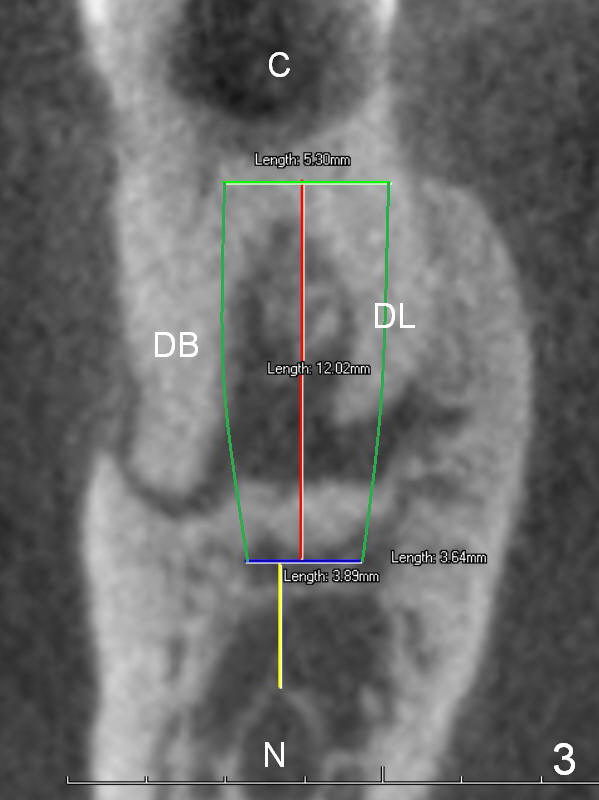

A 68-year-old lady (WQ) had CT taken 3 years ago (Fig.1-3), which show 3 roots (M: mesial; DB: distobuccal; DL: distolingual) of the lower right 1st molar and large caries (C). Recently the tooth fractures after root canal therapy (Fig.4-6).

Having 3 roots suggests a tripod septum. Surgical handpiece and elevators may be required, in addition to proximators. Cowhorn forceps should be helpful. The socket will be treated with Clindamycin, selected by time sequence.

An implant placed the tripod septum should be stable. The length of the initial osteotomy is 12 mm using 2 mm pilot drill. Take intraop PA as early as possible for trajectory and depth determination.